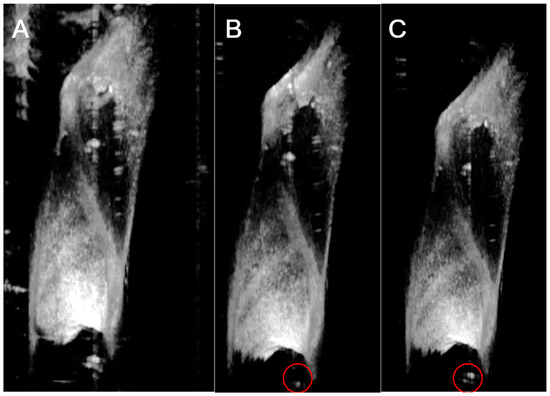

2.3. Large Object Detection Algorithm

2.4. Small Object Detection Algorithm